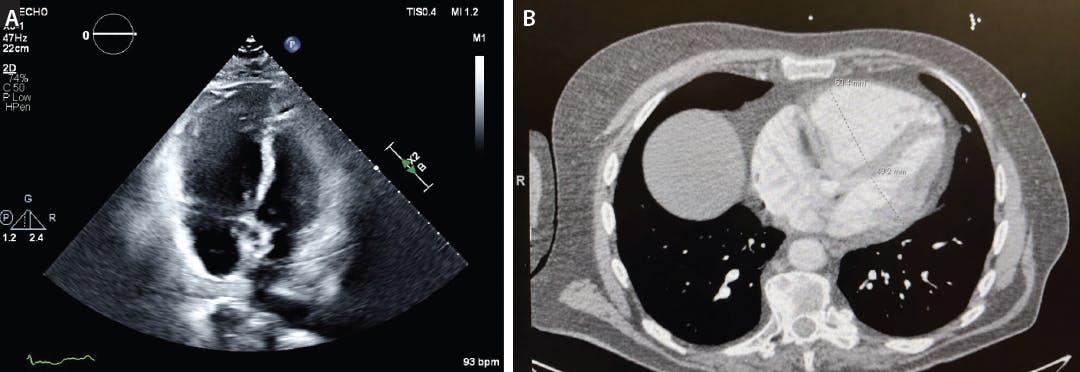

Laboratory evaluation showed elevated D-dimer (4.8 µg/mL) and mildly increased troponin I. CT pulmonary angiography (CTPA) demonstrated a saddle PE extending into both main pulmonary arteries (PAs) (Figure 1). Echocardiography revealed marked RV dilation with a RV/LV (right ventricular/left ventricular) ratio of 1.4, consistent with RV strain (Figure 2).

Figure 2. Echocardiogram (A) and CT image (B) showing RV dilation with an RV/LV ratio of 1.4.